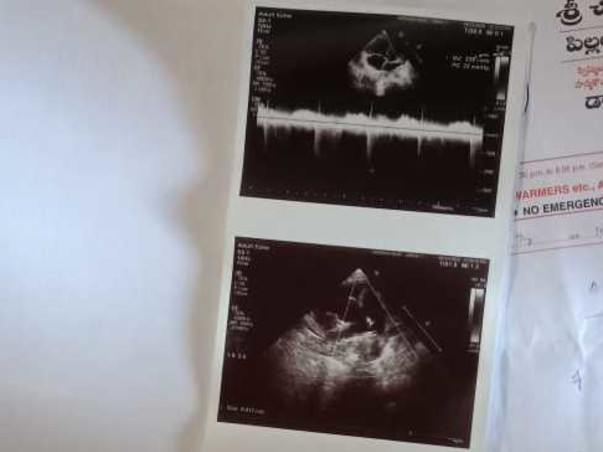

To make a living, her father works as a Daily Wages. Deekshitha is suffering from an Atrial Septal defect for a few days.

She is receiving Medication at Sri Chiranjeeva Children's Hospital but not yet admitted. Until now, we've spent about Rs. 40000.